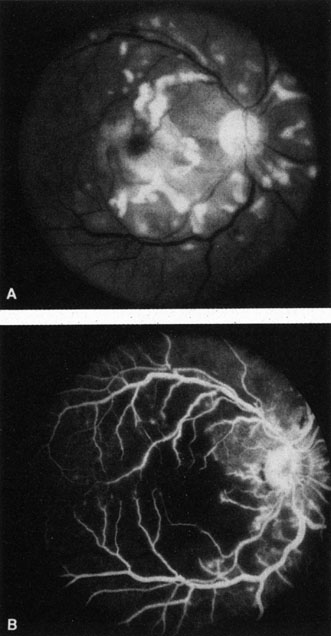

The clinical picture is typically striking. Patients present with a sudden painless loss of vision. The appearance of a cherry-red spot in the fundus is characteristic (Fig. 1).2 The cherry-red spot appears because soon after obstruction of the blood flow to the inner retina, the normally transparent retina becomes opaque and blocks the brownish-red color from the underlying choroid, which is still supplied by blood. Because the retina overlying the foveola is relatively thin, however, the normal color of the choroid is still visible in this area.3,4 Although characteristic, the cherry-red spot is not pathognomonic for central retina artery obstruction.5 Sometimes the characteristic cherry-red spot does not develop; there may be only a slight accentuation of the brownish-red color in the foveola.4 It is not known how long it takes this cherry-red spot to appear, but in a primate model, it has appeared as early as 30 minutes after obstruction.6 An afferent pupil defect is usually present.2

Fig. 1. A: Acute central retinal artery obstruction with a cherry-red spot. B and C: Intravenous fluorescein angiography. There is a delay of dye appearance in the central retinal artery, and when it does appear, it does not fill the arteries completely. D: Ocular coherence tomography (OCT) at the time of occlusion showing the increase in retinal thickness and reflectivity of the inner layers of the retina. E: Seven months later there is significant optic atrophy(G), and the OCT (F) shown now has marked thinning of the retina.

With time, the retinal opacity diminishes, generally leaving an optic nerve that is atrophic (Fig. 1). Frequently, thinned retinal arteries and veins also remain.7,8 No foveolar light reflex is evident, and a finely pigmented appearance of the macula is typical.7 In some cases, arterial collaterals develop at the optic disc.9–11 Rarely, anatomoses that exist between the central retinal artery and the ciliary arteries become visible as preretinal loops (Nettleship collaterals) after an occlusion at the edge of the disc.12,13,378In approximately 20% of patients, an embolus is evident somewhere in the arterial system.14 Emboli are discussed later.

Intravenous fluorescein angiography is useful in showing the details of the abnormal circulation of a central retinal artery obstruction (Fig. 1). The principal abnormality is the delay in the appearance of the dye in the central retinal artery and its branches.2 Rather than the central retinal artery and its branches filling rapidly, considerable time may elapse before the entire arterial system is filled.15 The filling of the retinal arteries is often abnormal, with the fluorescein partially filling an artery (a dye front) or hugging the vessel wall, as in normal venous filling.15

Optic coherence tomography (OCT) of an acute central retinal artery occlusion shows a slight increase in the thickening of the retina and reflectivity of the inner layers of the retina that correspond to the opacity seen clinically (Fig. 1).409 With time, the disc becomes atrophic and the retina thinner.